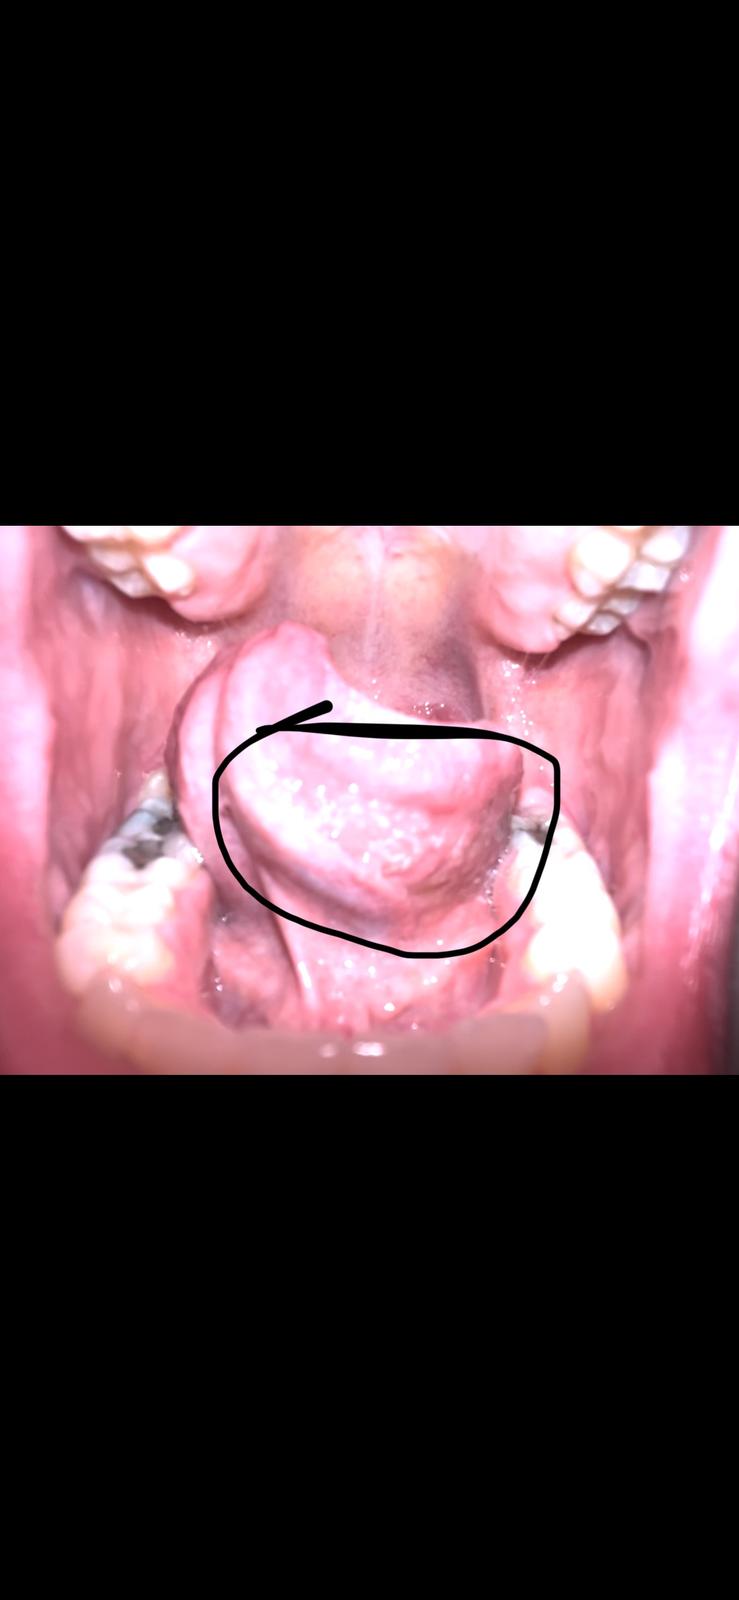

Vedeli by ste mi poradiť, čo sú toto za pľugieriky? Sú to afty?

Biele pľuzgieriky pod jazykom. Fotka trochu skreslila farbu, jazyk nie je taký červený a pľuzgieriky také veľké, no je ich dosť.

Ja som už skúsila B-komplex, Vit C aj vit D a stále sa to vracia. Čím to môže byť?😭je to mierne bolestivé.